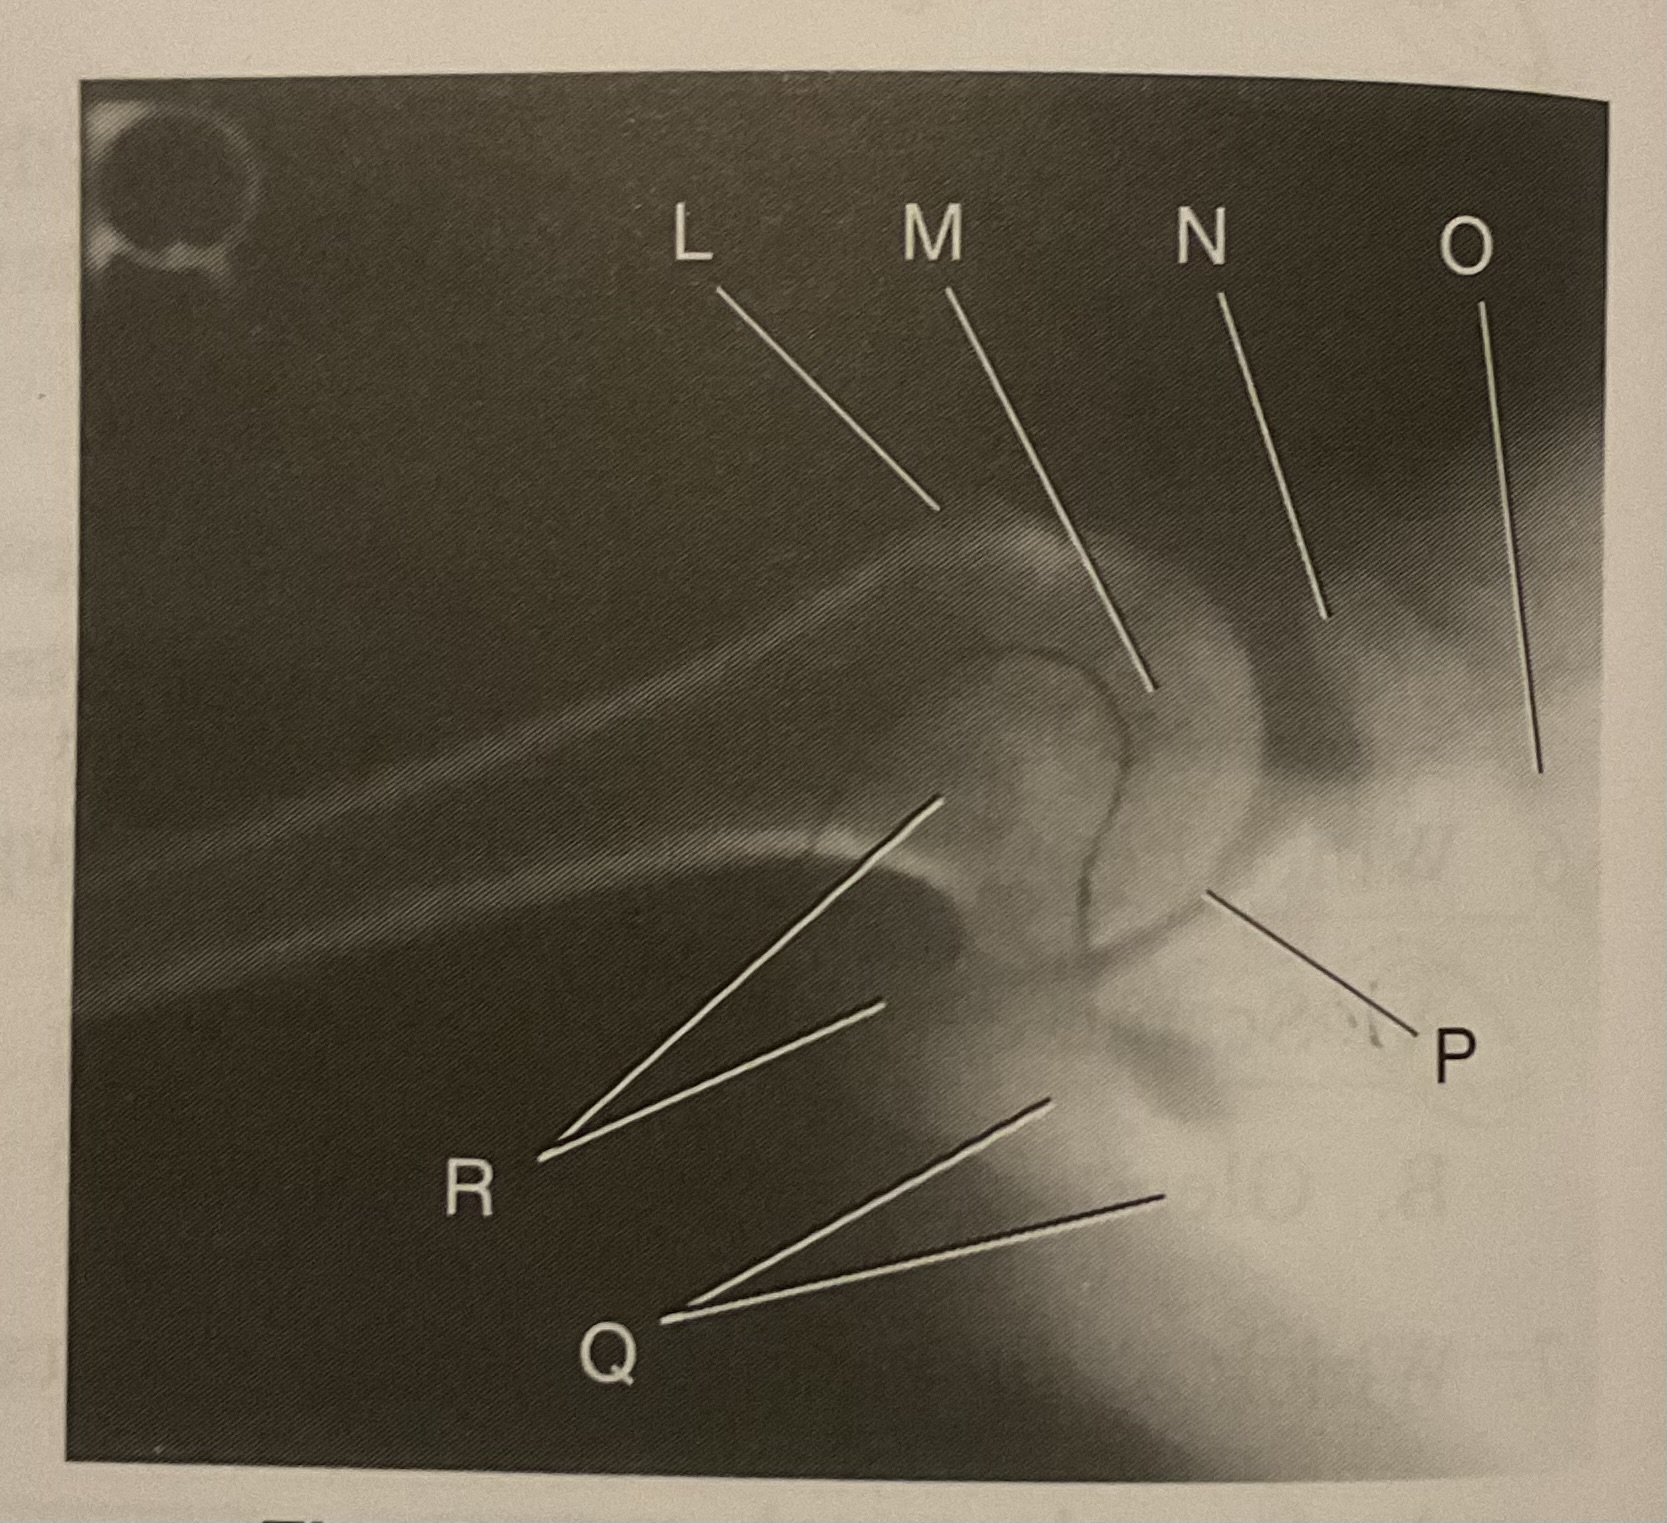

What AP projection does this image represent?

External

L?

Lesser tubercle

M?

Head of humerus

N?

Coracoid process

O?

Clavicle or lateral extremity of clavicle

P?

Glenoid cavity or Scapulohumeral joint

Q?

Spine of scapula

R?

Acromion of scapula

What is the correct term and method for the projection seen in this image?

Inferosuperior axial projection